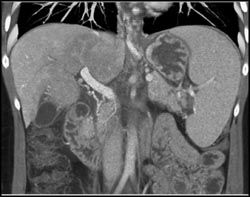

Hemangioma Fills In